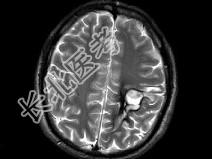

- 单项选择题男,49岁, 右侧肢体无力10余天,伴头昏行走不稳, 根据所提供图像,最可能的诊断是 ( )

E、颅内多发海绵状血管瘤